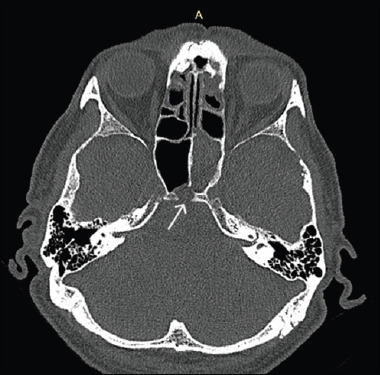

Background: Ecchordosis physaliphora (EP) is a benign hamartomatous lesion, most commonly found in a retroclival position, as an incidental radiological finding. EP may become symptomatic, by creating a clival defect, leading to CSF leak and meningitis, thus requiring surgical treatment.

Results: We present 5 cases of retroclival EP (4 males, 1 female; age range, 34-81 years) presenting in our department over the last 6 years. Four patients presented with CSF leak; 3 also had a history of bacterial meningitis, while one was diagnosed with meningitis on presentation. One patient was and remains asymptomatic 28 months later with the lesion being an incidental finding. The EP was treated in all 4 symptomatic patients with removal of the lesion and reconstruction of the defect with an endoscopic endonasal transclival approach (EETTA). All 4 patients remain free of symptoms while the lesion has not recurred for 81, 72, 52, and 22 months, respectively.